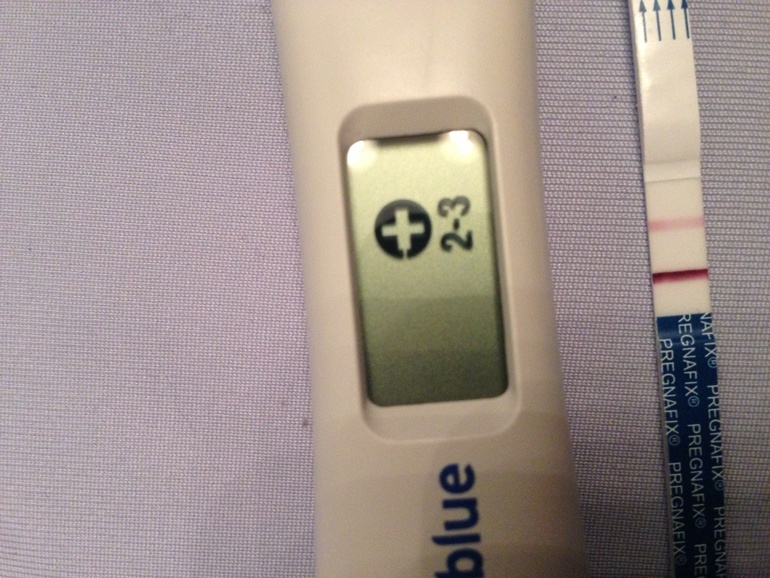

Вот теперь позади наше первое УЗИ! Увидели мою маленькую жемчужинку.Боже, как же это эмоционально!!!! По узи у нас ровно 5 недель, плод яйцо 0,32 см.Через неделю идем слушать сердечко!!!! Малыш, ещше совсем маленький, ты только расти!!!! Мы тебя уже очень, очень любим и ждем!! Ты для нас самый-самый!!!!